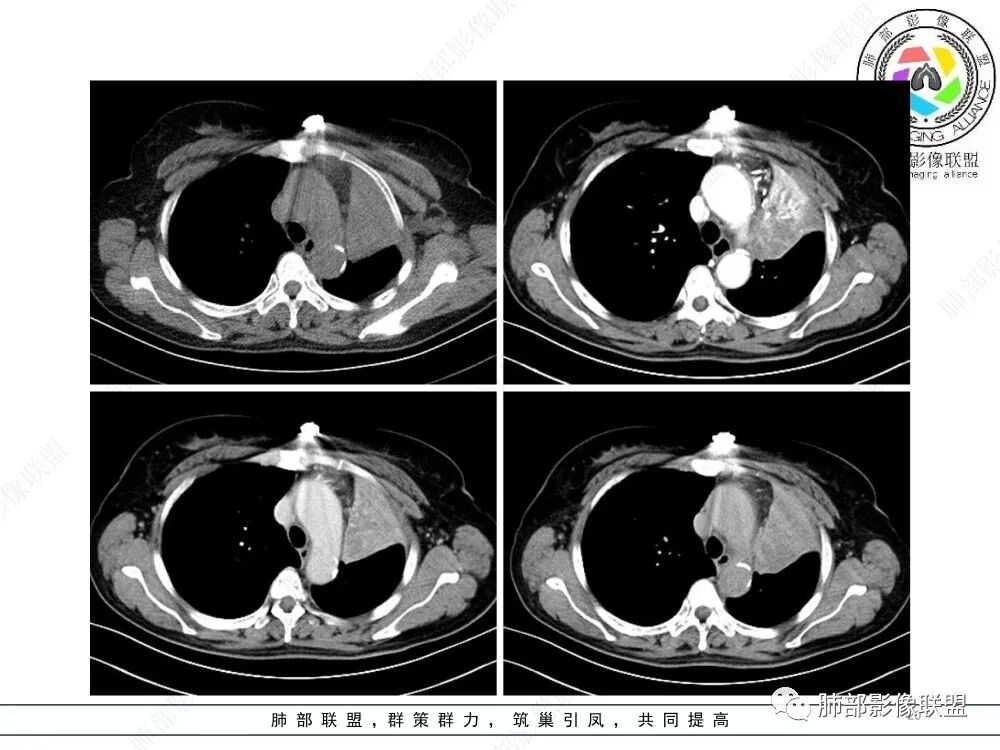

2、影像表现:正常肺背景,左肺上叶支气管腔内占位,上叶支气管截断,远端肺组织不张,强化差异衬托出肺门区结节影或块状影。增强扫描腔内占位轻中度不均匀强化,可见坏死,远端粘液栓,局部肺动脉受压、侵犯,纵膈淋巴结无明显肿大,无胸腔积液。

3、综合分析:老年女性,支气管腔内占位明确,病灶向周围侵犯,诊断恶性肿瘤并肺不张问题不大。需要考虑到的疾病谱有鳞癌、腺样囊性癌、粘液表皮样癌、类癌、小细胞肺癌等。